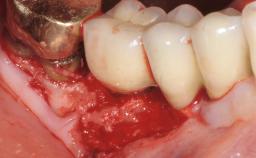

A 72-year-old female patient was referred to the specialist clinic with signs of peri-implantitis associated with implant 14. Two implants (sites 14 and 15) had been in function for three years. The patient was in good general health and was not taking any medication. She was a former smoker (12–15 cigarettes a day for 50 years) but had ceased smoking two years prior to implant placement. Her periodontal condition was stable, with no probing depths above 5 mm and a full-mouth plaque score (FMPS) of 35%.